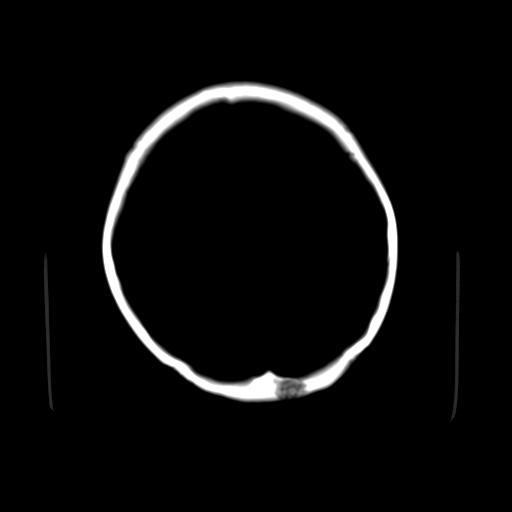

女,42岁,前额部外伤1小时,伤后头痛。

颅内未见明显异常,枕骨松质骨瘤可能性大。颅骨板障起源骨瘤较常见,骨血管瘤有垂直骨针及粗大钙化,嗜酸性肉芽肿软组织有改变,典型者可见“纽扣状”死骨,年龄通常较小。

左枕骨松质骨不均匀低密度灶,边缘清楚,考虑良性松质骨性骨瘤可能性大。

不排除左枕骨嗜酸性肉芽肿可能。

考虑枕骨血管瘤